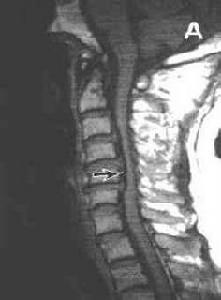

磁共桭:可清晰顯示間盤組織後突,壓迫硬脊膜囊和脊髓的情況,以及有無靜脈回流受阻、受壓局部脊髓內有無囊性變等情況。